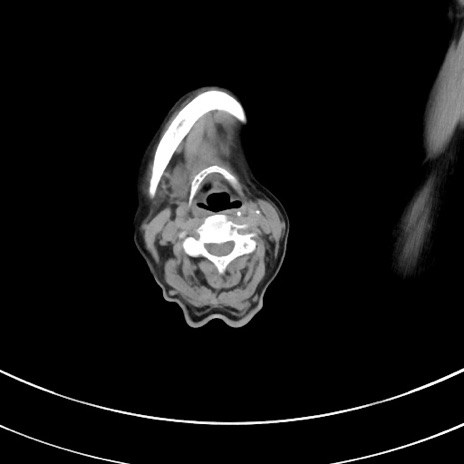

症例33(横断像)

【症例】70歳代 女性

【主訴】心窩部痛

【現病歴】延髄病変の精査・加療にて神経内科入院中。本日より心窩部痛あり。

【既往歴】虫垂炎

【身体所見】右下腹部を中心に圧痛と反跳痛あり。

【データ】WBC 10900、CRP 0.02